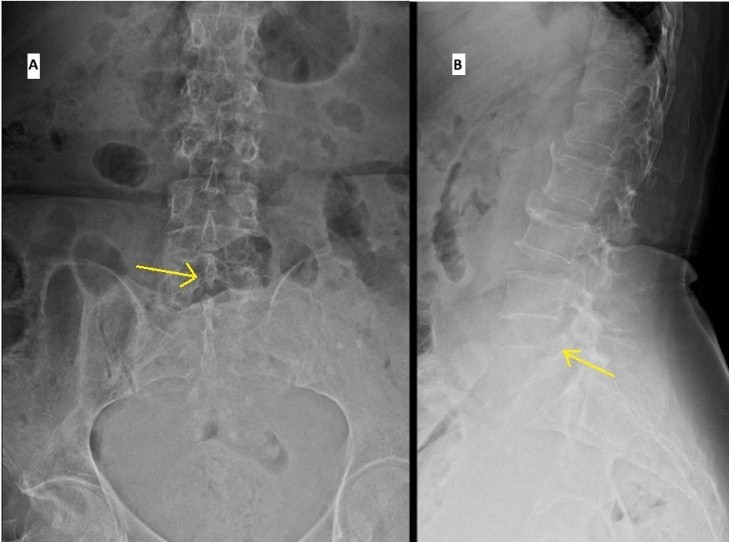

Plain X-rays of the lumbosacral spine showed collapse and loss of height of the L5 vertebral body (Fig. 1).

Figure 1: Plain radiographs anteroposterior (a) and Lateral (b) projections showing collapse of L5 vertebrae (marked with arrow).